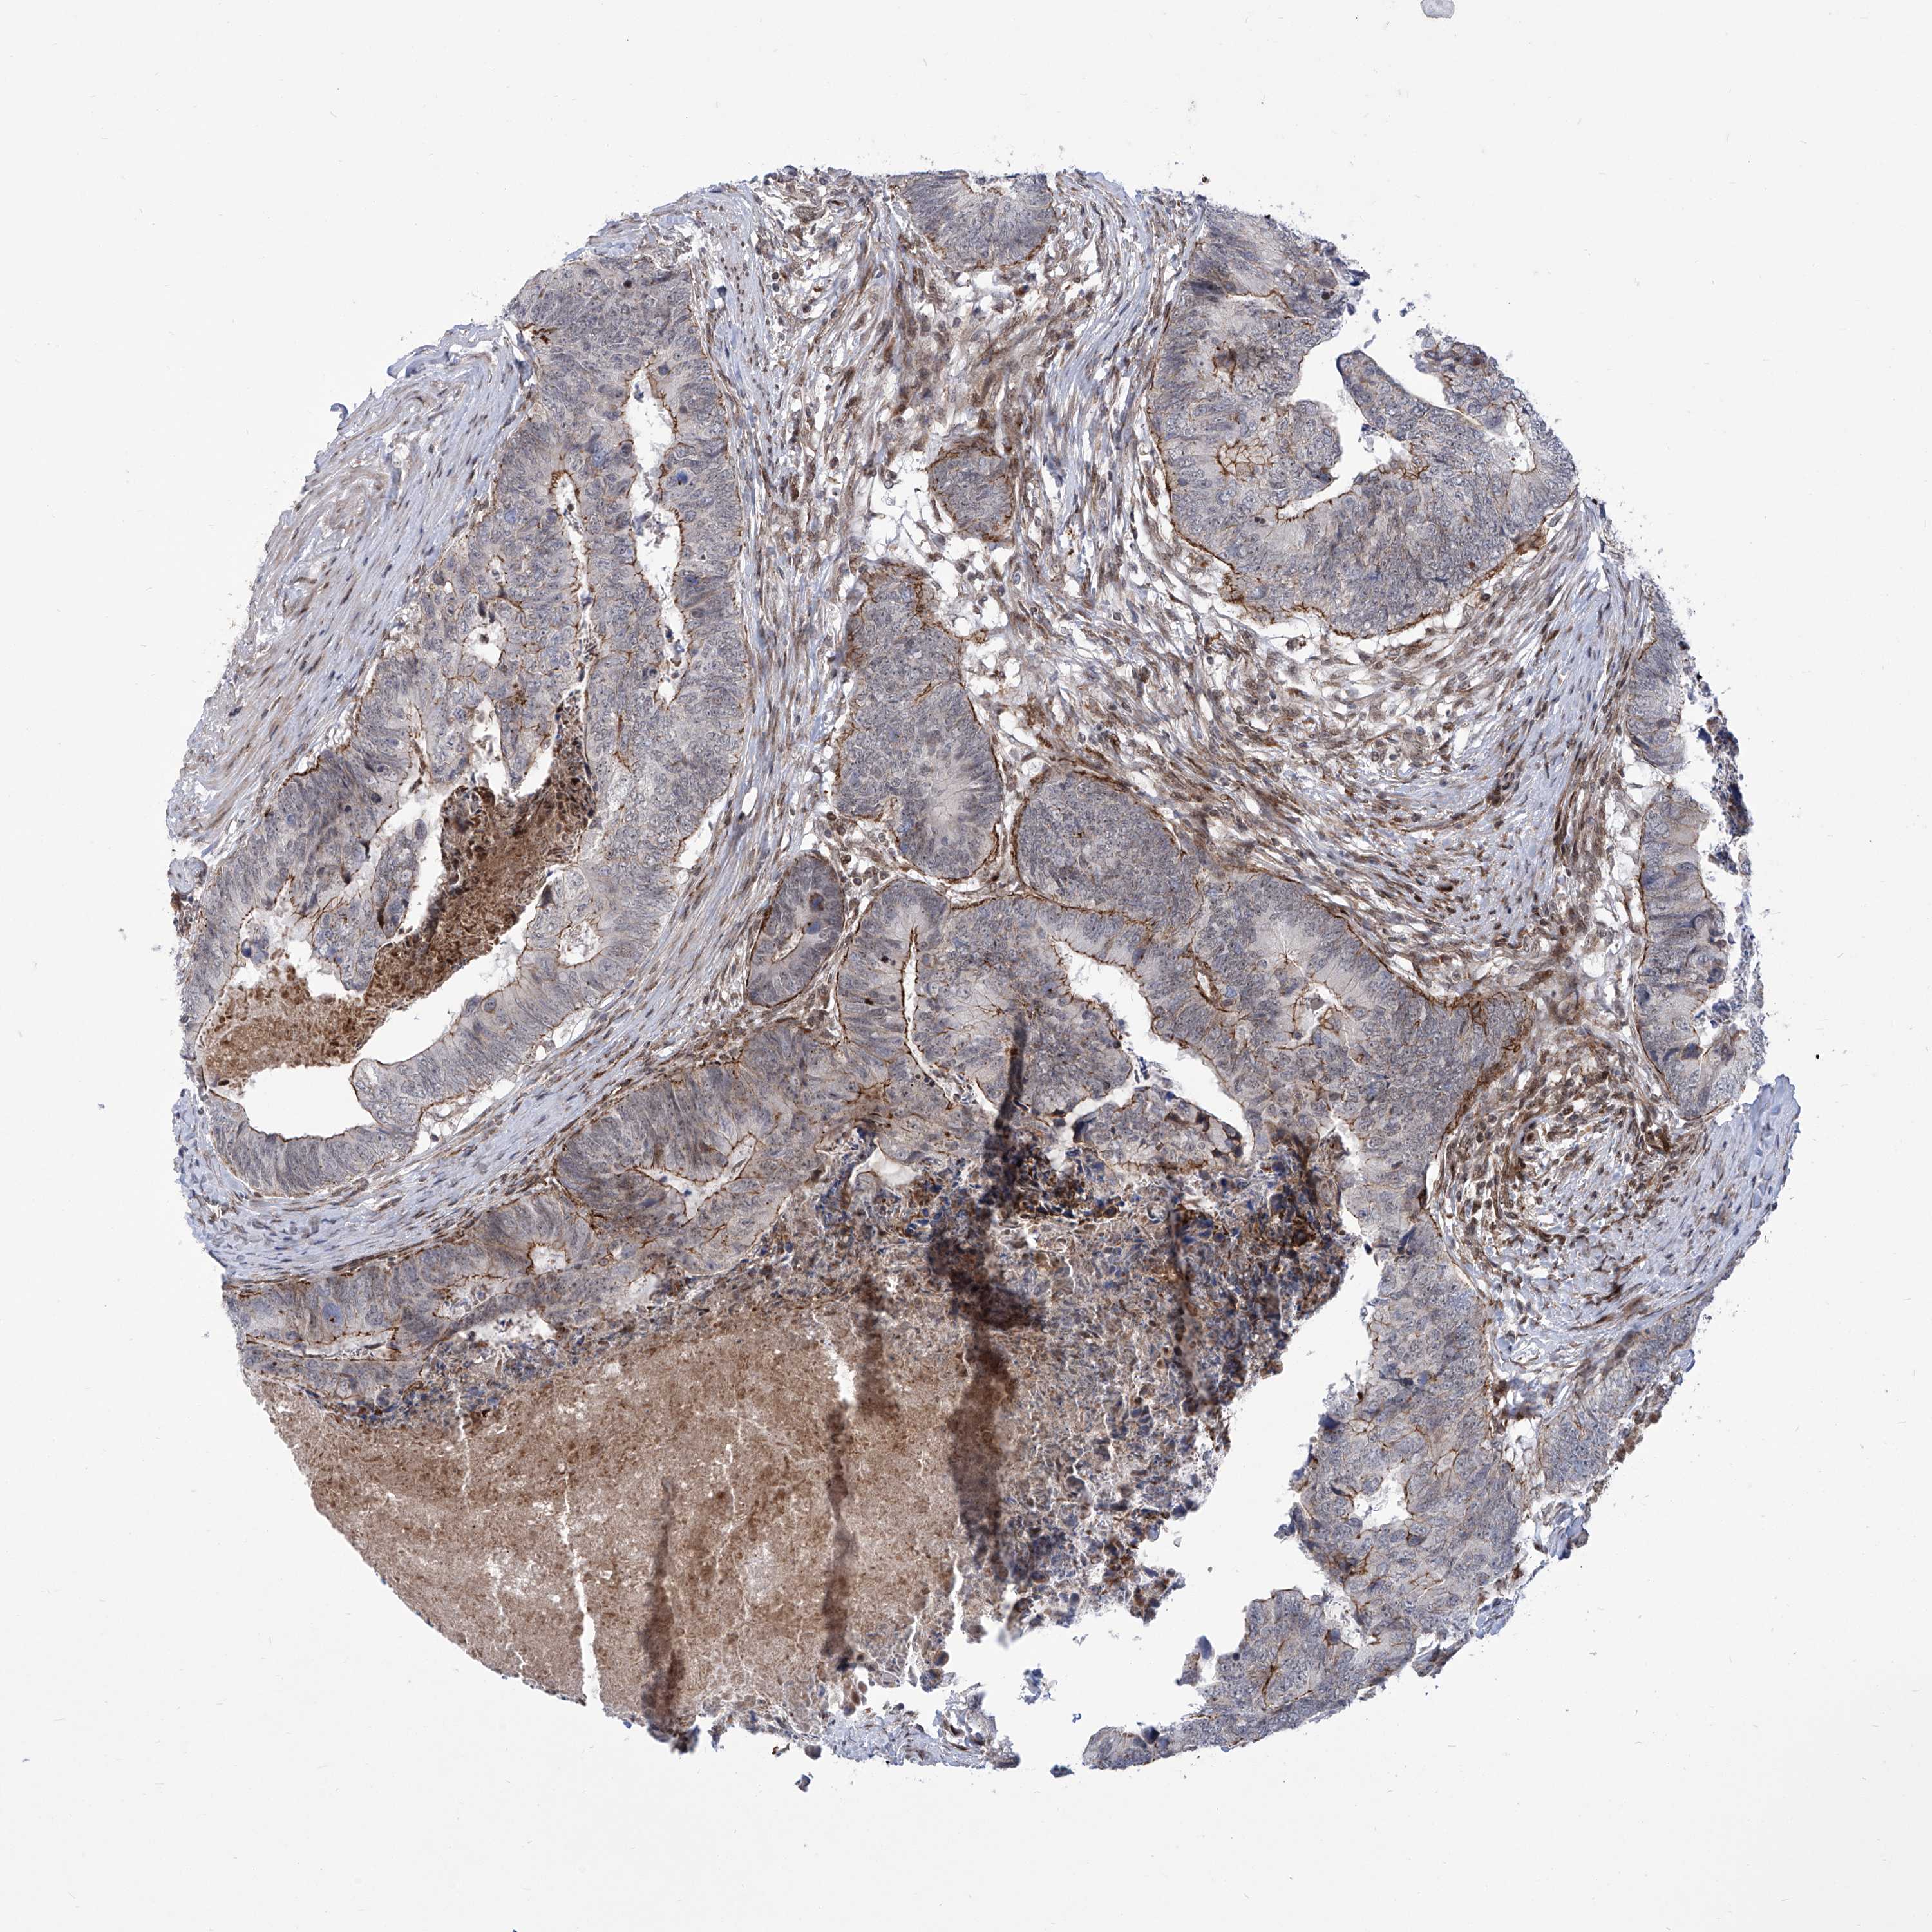

CANCER COLORECTAL CANCER Show tissue menu

Colorectal cancer

Human cancer

Colon adenocarcinoma